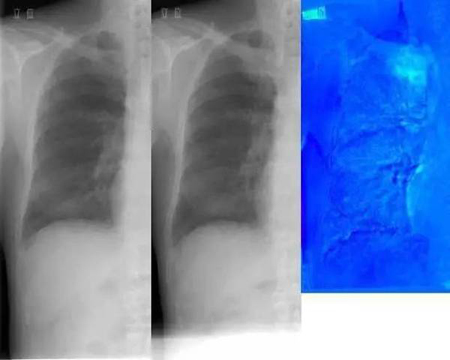

这款差分剪影对比诊断引擎更是不得了,它能够让影像“开口说话”。其基于云端影像存储,可智能检索、融合比对患者过往影像与历史影像,自动凸显描绘病灶剪影,准确勾勒毫米级病灶变化趋势,辅助疾病早筛及疗效跟踪,加倍提升诊断效率、减少漏诊。这一技术已在上海交通大学医学院附属瑞金医院等各大医院投入临床使用,辅助重疾早筛、管理并全面评估受检者全生命周期健康情况。